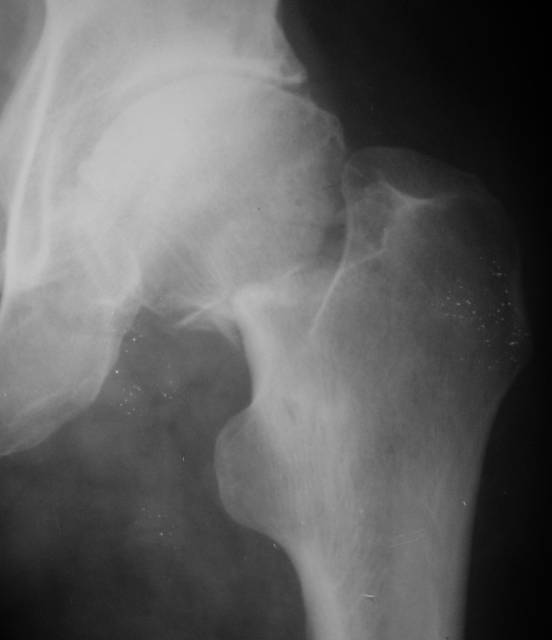

Re: несросшаяся шейка бедра

До травмы проблем с ногой не было. Укорочения, болей и т.п. не отмечал. Сегодня перемерял укорочение - меньше 7 см намерять не

По уровню малых вертелов (с учетом рентгеновского увеличения) получается 5 см. Клинически ногу низвести путем тракции невозможно. Из движений - сгибание до 40*, остальные движения "символические".